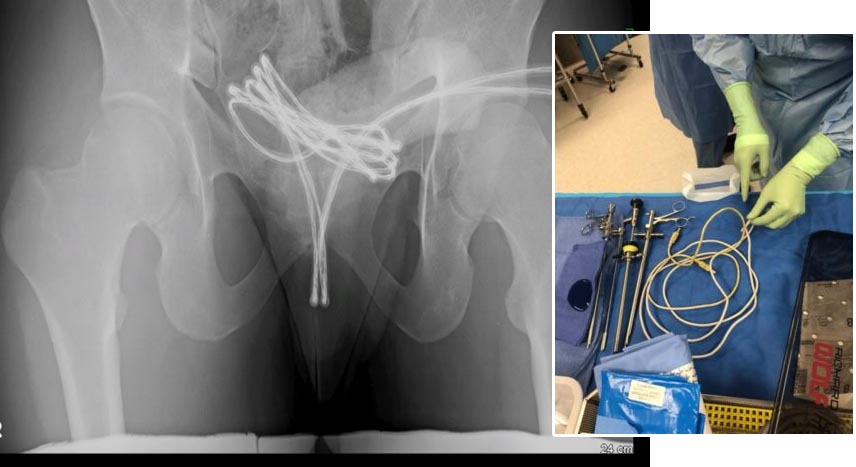

Cirurgia foi necessária para remoção do cabo USB

Após exames, os médicos constataram que o cabo estava alojado na bexiga, o que dificultava sua remoção. Foi necessário realizar uma cirurgia com anestesia geral, utilizando uma câmera inserida na uretra para guiar a retirada do objeto. Apesar da gravidade, o jovem sofreu apenas ferimentos leves e segue em recuperação.